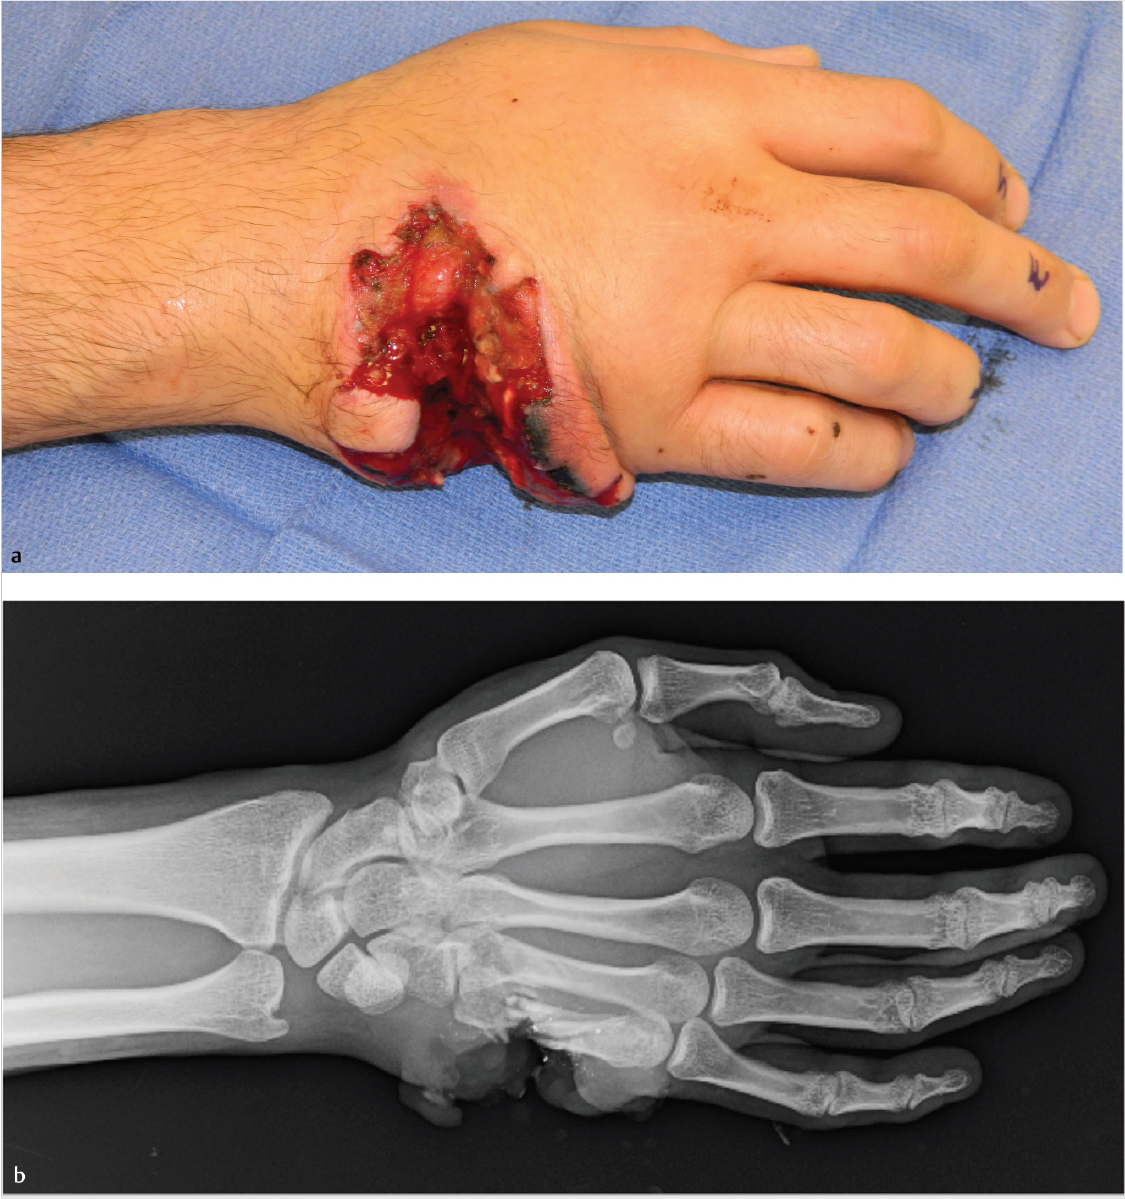

Soft-Tissue Defect of the Hand

Ulnar hand soft-tissue defect secondary to acute gunshot trauma.

No vascular compromise distally.

Fractures of the fourth and fifth metacarpals.

Presumed injury to extensor (and possibly flexor) tendons of ring and small fingers.

Likely neurovascular injury to ulnar digits.